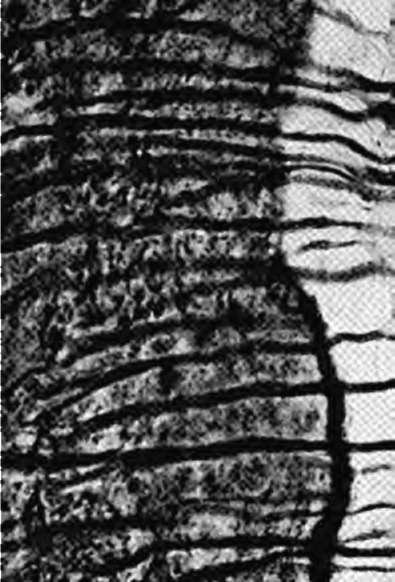

К локализованным формам хронического пародонтита относят поражения, охватывающие не более 30% площади пародонта. Причинами развития хронического локализованного пародонтита чаще всего являются местные факторы: аномалии прикрепления уздечек губ, языка и подслизистых соединительнотканных тяжей, мелкое преддверие полости рта, дефекты пломбирования зубов (отсутствие точечного контактного пункта и экватора зуба, нависающие края пломбы и т.д.), дефекты протезирования зубов и челюстей (широкий край коронки, длинная коронка, мостовидный протез большой протяженности, консольный протез, частичный съемный протез с плохой фиксацией и т.д.), дефекты ортодонтического лечения, аномалии положения и скученность зубов, нарушение прикуса и т.д. Эти факторы, воздействуя на пародонт длительный период времени, ведут к возникновению локализованного пародонтита или могут отягощать генерализованные формы пародонтита (рис. 14-19).

image

Рис. 14-19. Рентгенологическая картина хронического локализованного пародонтита